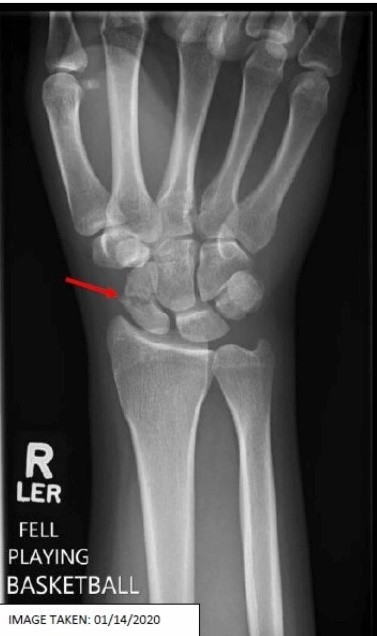

What fracture is this?

Scaphoid Fracture